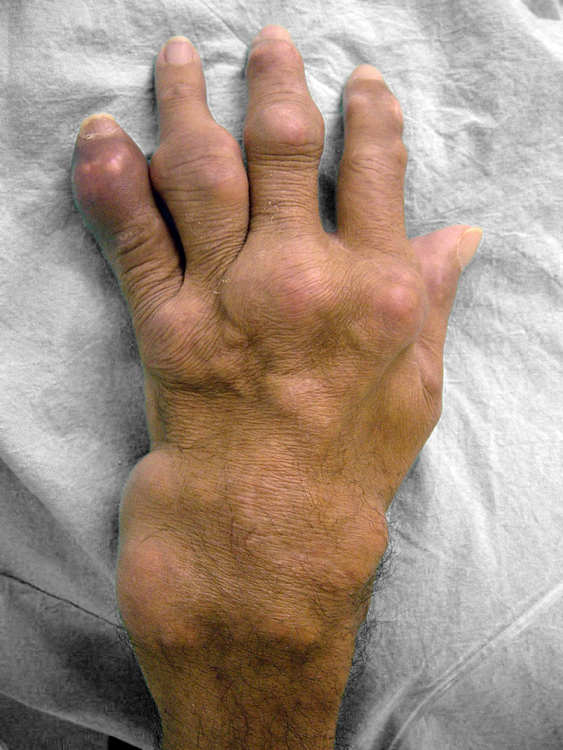

O exame físico pode revelar a formação de tofos, que são formações nodulares de cristais urato, depositados em alguns tecidos como: borda da orelha, ponta do nariz e superfície das articulações, principalmente dos cotovelos, dos joelhos, das mãos e dos pés.

O tratamento cirúrgico está indicado quando ocorre grande deformidade articular por degeneração e destruição óssea. Deformidades graves e dolorosas impedem o paciente de realizar tarefas cotidianas como calçar calçados ou pegar objetos com as mãos. Em alguns casos pode ser indicada a amputação da porção atingida, principalmente se houver úlceras ou infecção dos tofos gotosos.